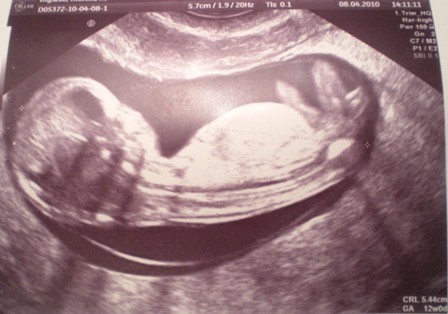

a oto moja slodycz- 12 tc

• 12t0d..JPG

12t0d..JPG

50,6 KB · Wyświetleń: 115